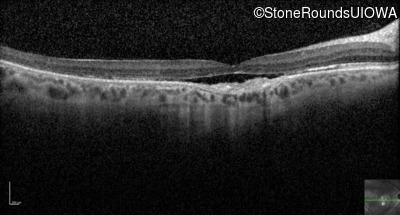

Optical Coherence Tomography - Left - 20/100

Exemplar / OCT Stack